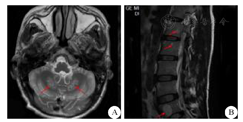

患者男性,32岁,务农,未婚。以"双下肢无力并行走不稳3年"为主诉于2018年5月2日收入我科。3年前无明显诱因逐渐出现双下肢无力并行走不稳,持续性存在,休息后不能缓解,不影响日常生活,无晨轻暮重、感觉异常、肌肉萎缩等。双上肢无明显异常。自觉上述症状逐渐加重,逐渐出现步态异常,易跌倒,方向不定。既往史、个人史无特殊。父母均为汉族,体健,非近亲结婚,1兄、1姐及其兄姐双方的子女均体健,余家族史亦无特殊。体检:生命体征均在正常范围内。体型偏小、瘦弱,皮肤黏膜无色素沉着。认知粗测正常,精神状态良好。两侧肌肉对称,未见明显萎缩、肥大;双上肢肌力5级,肌张力正常,双侧肱二头肌、肱三头肌、桡骨膜反射均亢进(++++),双侧Hoffmann征、Rossolimo征均阳性。双下肢肌力4级,肌张力增高,双侧踝阵挛阳性,双侧膝腱反射、跟腱反射均亢进(++++),双侧Babinski征及其等位征均阳性。腹壁反射亢进(+++)。双侧跟-膝-胫试验欠稳准,闭目难立征阳性,剪刀步态。深、浅、复合感觉正常。脑膜刺激征阴性。双侧跟腱可视、触及对称性增粗,余肌腱未触及明显增粗。血同型半胱氨酸27.14 μmol/L(正常值范围为0~15 μmol/L)。头颅3.0 T MRI平扫提示双侧小脑齿状核异常信号(图1A)。全脊椎1.5 T MRI平扫提示颈、胸、腰椎退行性病变;腰1~5椎体多发异常信号,考虑脂肪岛;骶管囊肿(图1B)。胸部CT提示右肺中叶小结节及条索状病灶。腹部脏器彩超提示胆囊壁毛糙,附壁可见数个点状强回声。双侧跟腱彩超提示双侧跟腱弥漫性增粗,回声减低,腱纤维回声紊乱,后方回声明显衰减,内可见少许彩色血流信号。右侧跟腱活检可见炎细胞及大量组织细胞浸润,大量胆固醇结晶,符合跟腱黄色瘤病理特征(图2)。对CYP27A1基因的外显子编码区进行一代测序,结果提示2个位点的突变:c.1263+1G>A和c.1420C>T (Arg474Trp)(图3)。进一步检查提示其父亲存在c.1263+ 1G>A突变,母亲存在c.1420C>T突变。

Results of HE staining and immunohistochemical staining of biopsy tissues in the patient (×200)

A:HE染色结果;B:CD68免疫组化染色结果;C:CD163免疫组化染色结果